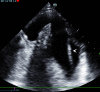

A man with sudden onset chest pain